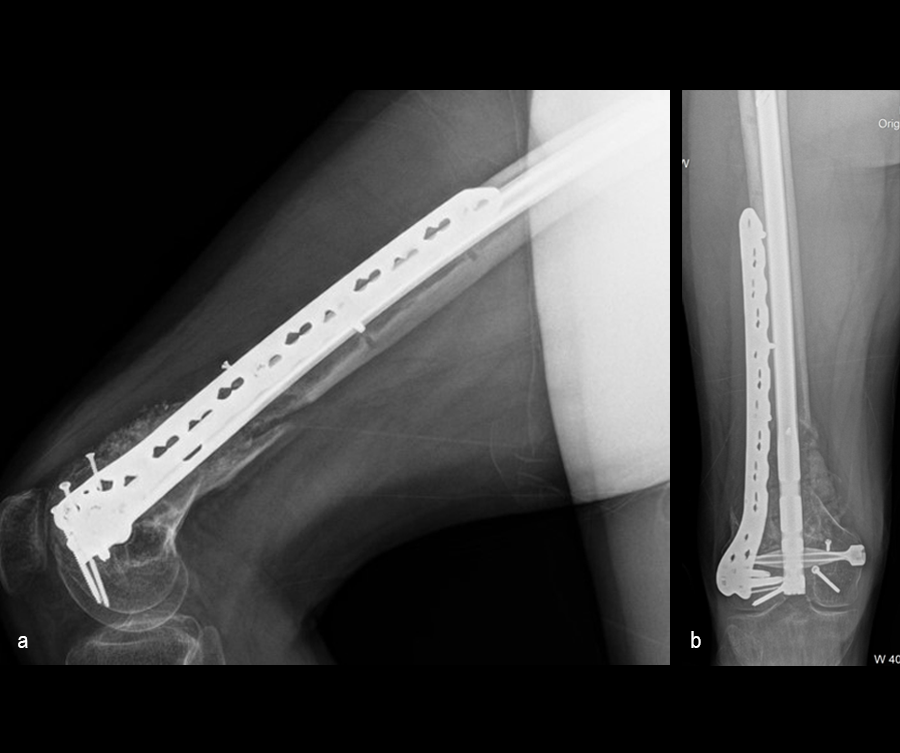

Case 1—Open right supracondylar intracondylar distal femoral fracture following motor vehicle accident

(Case kindly provided by Brent Norris, Orthopedic and Trauma Services of Oklahoma, USA)

A 34-year-old man was involved in a motor vehicle accident in December 2019 and sustained these injuries (Fig 5):

> Left-sided rib fractures with lung contusion

> Open right supracondylar intracondylar distal femoral fracture with possible vascular injury (limb-threatening injury)

> Closed right bimalleolar ankle fracture

> Closed right talar fracture

> Open left plafond fracture

> Open left talar fracture dislocation

> Open left elbow joint

He had no major previous medical history and worked in the furniture delivery business.

The day following admission, the patient underwent these procedures in the operating room (Fig 6):

> Washout of open injuries right side, including femur and ankle

> Open reduction of the talar injury

> Spanning external fixator of the femur and ankle

> External fixation of the left plafond/talus

At 3 days postoperative, the patient underwent a repeat washout of the right femur and right ankle. The lung injury was still recovering so no definitive fixation was performed at this time.

At 5 days post-initial surgery, the lung injury was improved, so the patient underwent open reduction and internal fixation (ORIF) of the right distal femur with resection of devitalized bone and cement spacer placement (Fig 7). Definitive fixation of the other fractures (ankle and ribs) was undertaken over time.